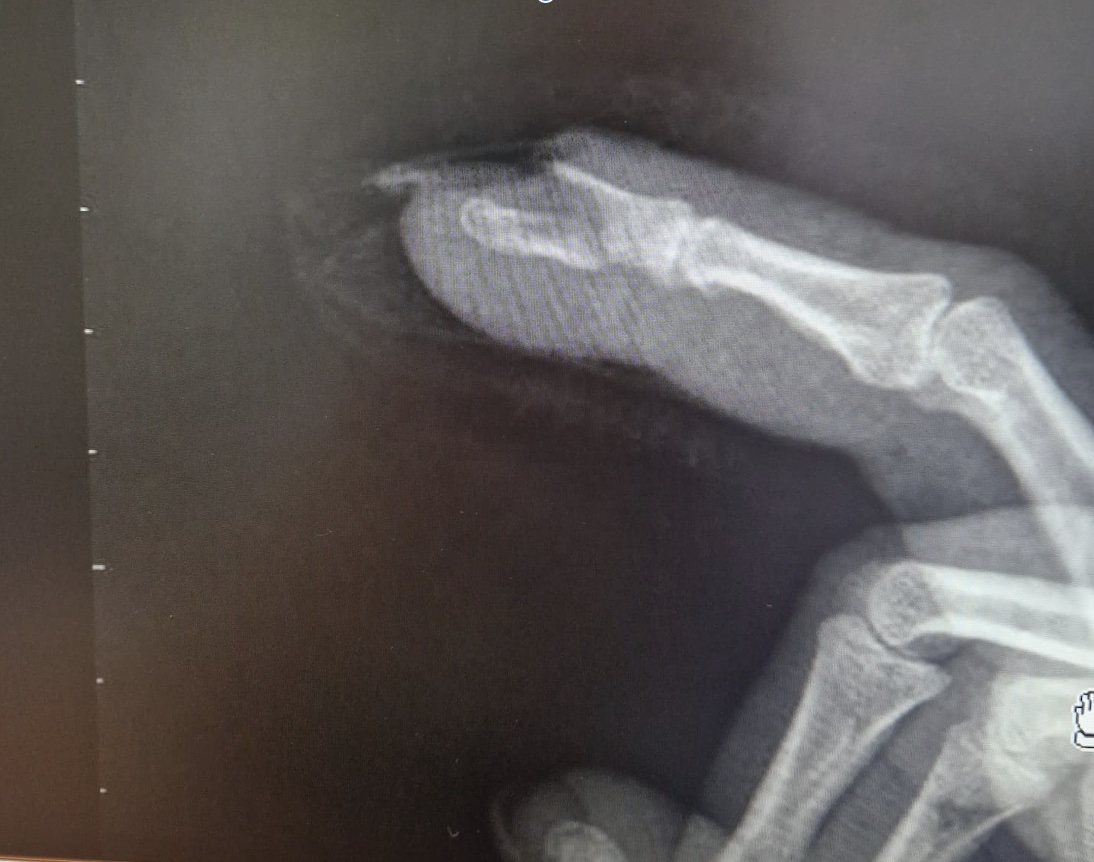

Se decide derivación a urgencias donde confirman fractura mediante radiografía de la mano.

Juicio clínico: Fractura desplazada de falange distal 2º dedo mano derecha.